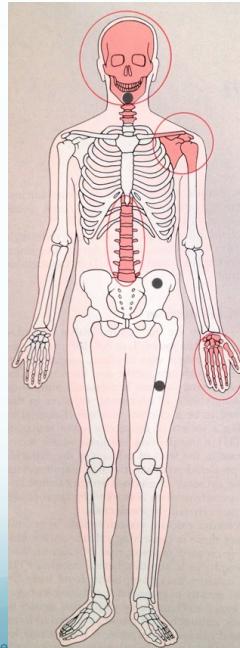

- Sub-periosteal resorption of:

- Middle phalanges

- Lateral end of clavicle

- Skull: “salt & pepper” appearance

- Sub-periosteal resorption: middle phalanges, tibial shaft

- Lateral end of clavicle resorption

- Skull: “salt & pepper” appearance